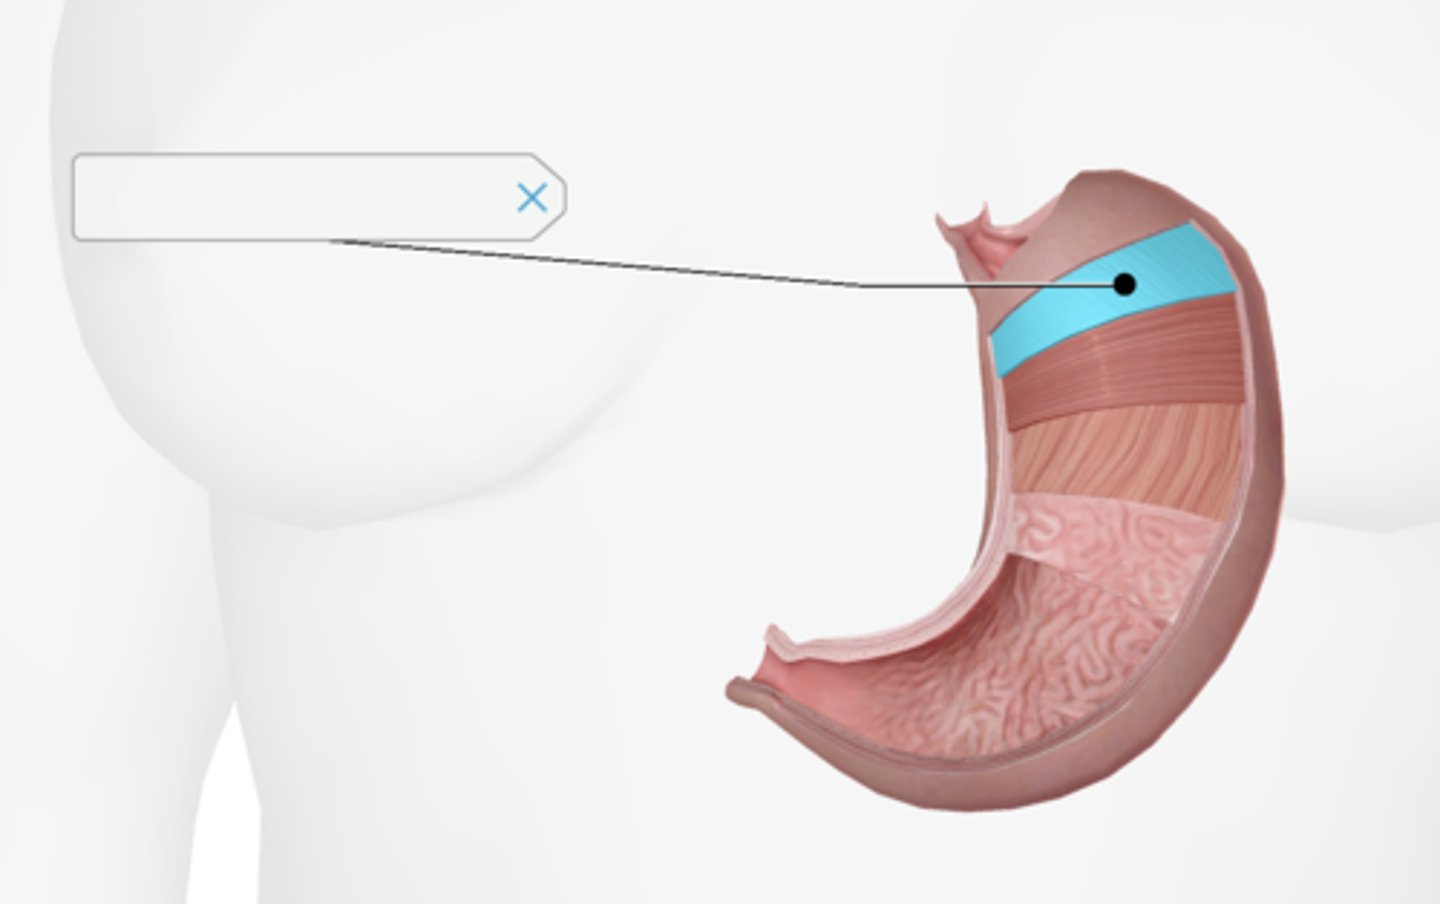

Longitudinal muscle layer of the stomach

Oblique muscle layer of the stomach

Circular muscle layer of the stomach